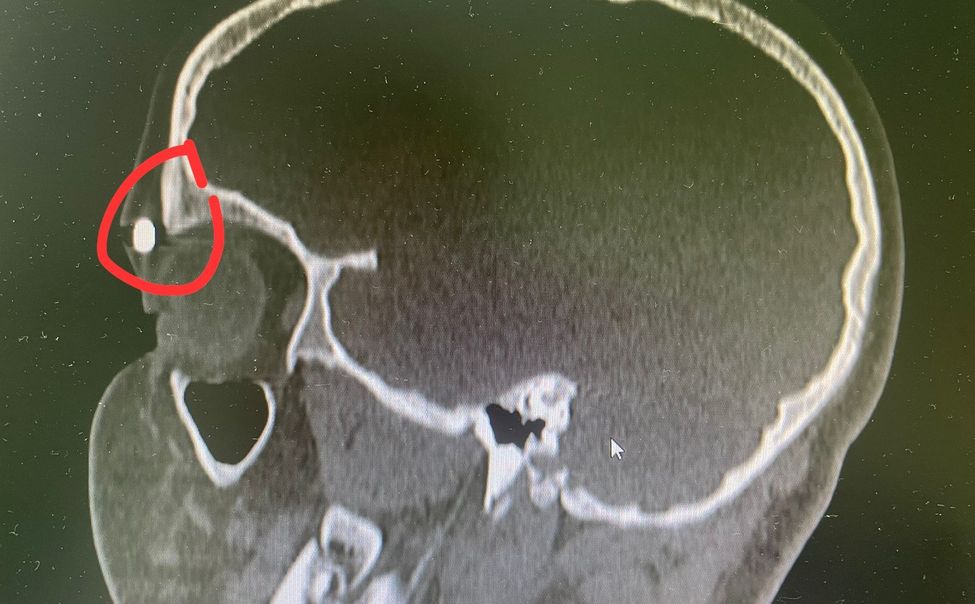

В приемно-диагностическое отделение Республиканской детской клинической больницы за медицинской помощью обратились подростки с пулевыми ранениями.

Ежедневно в отделение оториноларингологии и челюстно-лицевой хирургии Республиканской детской клинической больницы обращаются маленькие пациенты с родителями, которые, к сожалению, не могут обойтись без помощи специалистов.